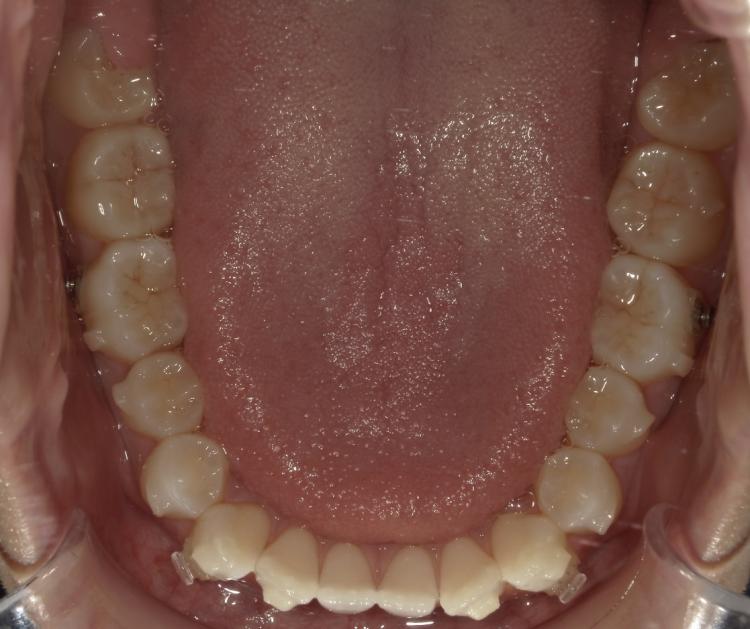

インビザラインのアライナーを23枚目に交換しました。

歯並びが変化してきて、下の親知らずがまっすぐ上に出てきました。

インビザラインを開始した時と現在の写真です。

もともとスペースが足りず歯ぐきがかぶっていて汚れがたまりやすかったのですが、磨きやすくなったように感じます。